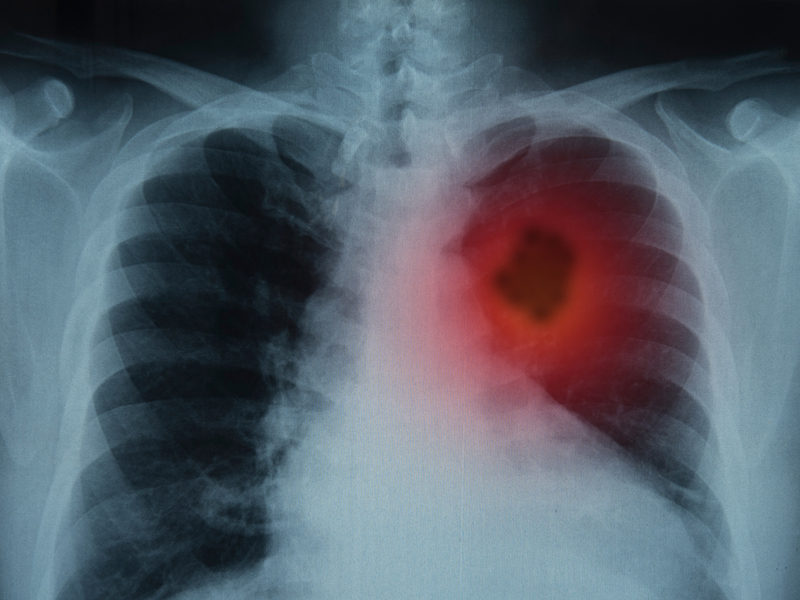

需要注意的是,苦杏仁含有苦杏仁苷(Amygdalin),具有一定毒性,若服用過量,會產生氫氰酸中毒,會出現以下症狀:

1. 暈眩

2. 心悸

3. 噁心

4. 嘔吐

相較之下,甜杏仁雖然也有苦杏仁苷,不過,含量卻只有苦杏仁的千分之一,這也是為何甜杏仁能直接當零食吃的原因。